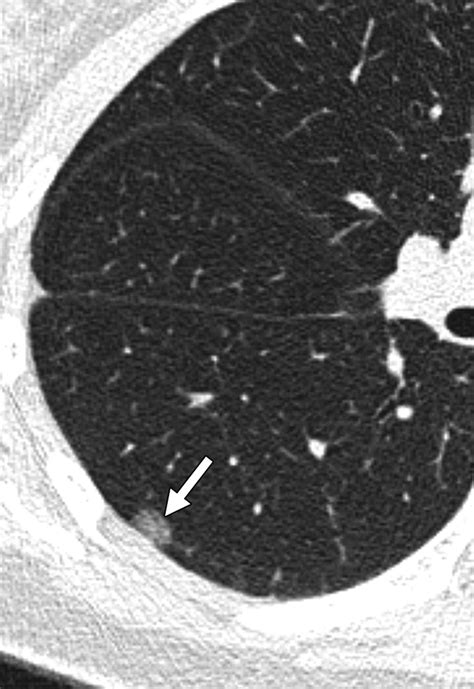

A ground glass nodule (GGN) refers to a hazy, cloudy opacity within the lungs that appears on a CT scan. Unlike solid nodules, which are dense enough to completely obscure the underlying lung tissue, a GGN allows the structures of the lung, such as the airways and blood vessels, to remain visible through the haze. The term derives from the visual similarity to glass that has been treated to appear frosted or translucent.

• Size: Whether the nodule is smaller or larger than 5-8 millimeters.

• Consistency: Whether the nodule is "pure" (completely hazy) or "part-solid" (containing a denser core).

The primary strategy for managing a ground glass nodule is "active surveillance." Because these findings often grow extremely slowly—sometimes over the course of several years—there is rarely a need for immediate, invasive surgery. By performing serial CT scans, your pulmonologist or thoracic surgeon can track changes in size, density, and shape.